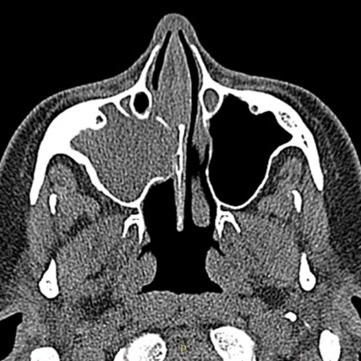

Características de Imagens

De forma geral, a sinusite odontogênica demonstra, em imagens de tomografia computadorizada, obliteração parcial ou total do seio maxilar afetado, além de espessamento da mucosa sinusal, nível líquido (sugestivo de infecção ativa), destruição ou erosão óssea do assoalho sinusal (sinal de origem odontogênica), lesão periapical associada a um dente posterior (principal achado diagnóstico), comunicação oroantral em casos de perfuração do seio, e até mesmo corpos estranhos, em casos de procedimentos odontológicos.